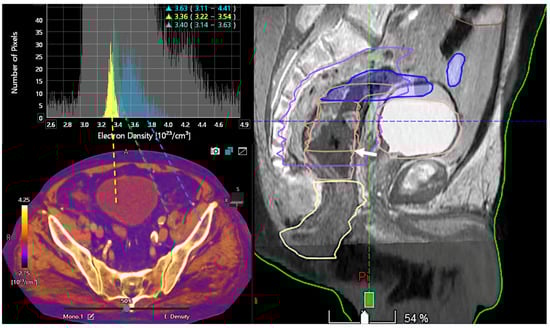

Advanced applications of DECT may also provide quantitative measurements for radiotherapy planning, such as the Zeff and electron density of tissues for stopping power ratio calculation (SPR). DECT improves the accuracy of the SPR with an uncertainty of 1–2% in the proton range. DECT can be particularly useful for dose-delivery techniques with a steeper dose gradient, such as brachytherapy and proton therapy [32]. In particle therapy, SPR is significant for dose calculations because the planning target volume (PTV) margin includes the uncertainty determined based on the SPR. Protons release the maximum energy just before they stop penetration, making an accurate estimation of the SPR essential for therapy planning. Enhanced tumor visualization and delineation or artifact reduction using DECT have the potential to improve volume segmentation and dose calculation for radiation therapy planning in cancer treatment (Figure 10).

Figure 10.

Color-coded electron density map based on DECT (bottom, left). Histogram analysis of electron density values at different locations (bladder lumen [water, yellow], muscle [green], and bone [blue]). Information on electron density is important for radiotherapy treatment planning in order to optimize the dose distribution and volume delineations. Sagittal fused CT and MR image (50% transparency) for therapy planning demonstrates the tumor (white arrow, right image).